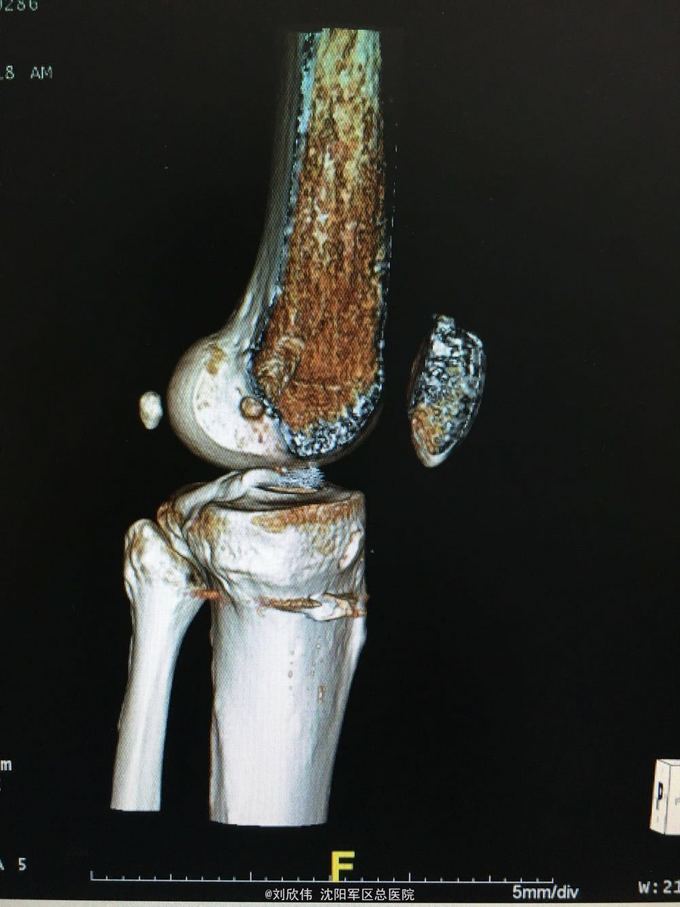

男性,44岁,摔伤所致,左膝。诊断如题

前抽屉,lachman,轴移阳性,外侧应力试验因疼痛无法进行

诊断如题,关节镜解决acl,mcl给予支具保守治疗

这个病例值得讨论的有2点,其一,mcl即内侧副韧带的处理通常可以保守治疗,二期不稳后再行手术治疗。第二,前叉胫骨侧隧道内口的位置,一个原则,宁内勿外。